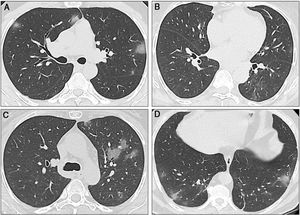

Sequential computed tomography scans performed in the three cases. A) Case 1: CT scan shows multiple ground-glass opacities (GGOs) in the upper and lower lobes, with bilateral and peripheral distribution. Some GGOs can also be seen next to the left hilum. These image findings are typical of SARS-CoV-2 pneumonia. B) Case 2: The initial CT scan shows subtle GGOs in the inferior right lobe. In the first follow-up scan, new areas of GGOs are visible in the superior left lobe. C) Case 2: The second CT scan shows that the GGOs increased in size, number, and density. Bilateral involvement is present (not shown). D) Case 3: The CT scan shows a single subpleural GGO. Multiple areas of ground-glass opacities with the classic COVID-19 appearance can be seen, as well as some linear opacities associated with the GGOs.

A 41-year-old man, with no past medical history, arrived at the emergency department (ED), with fever and shortness of breath, on March 22. Physical examination revealed fever, oxygen saturation (O2 sat) of 88%, and bibasilar crackles. He was admitted to the hospital. Laboratory tests upon admission reported lymphopenia (complete biologic data are available in Tables 1 and 2). A computed tomography (CT) scan identified bilateral ground-glass opacities (GGOs) and septal thickening (Fig. 2A). The nasopharyngeal swab test for SARS-CoV-2 was positive and treatment with hydroxychloroquine and azithromycin was started. Fever was present during the first two days of hospitalization, and supplemental oxygen delivered by nasal cannula was required for three days. The patient became asymptomatic after the third day and was discharged.

A 64-year-old woman underwent LT in 2018 due to liver cirrhosis secondary to hepatitis C virus (HCV) that was treated with velpatasvir/sofosbuvir. She had a medical history of type 2 diabetes mellitus (DM2) and arterial hypertension (HTN), and her immunosuppression regimen consisted of tacrolimus (levels: 6-8 ng/mL). On March 21, the patient arrived at the ED with cough, diarrhea, and fever. Laboratory test results showed leukopenia and lymphopenia. A CT scan revealed ground-glass opacities (Fig. 2B). The nasopharyngeal swab test for SARS-CoV-2 was positive. The patient was hospitalized for surveillance and treatment with hydroxychloroquine, azithromycin, and ceftriaxone. Due to drug interaction between tacrolimus and azithromycin, the tacrolimus dose was diminished. Two days after admission, a new CT scan showed progression of pneumonia (Fig. 2C) but no oxygen supplementation was required. The patient was discharged on March 26 (Tables 1 and 2).

Case threeA 60-year-old man with a history of HTN and kidney cancer in remission arrived at the ED on March 23, with a two-day history of fever and cough. Physical examination revealed fever and adequate oxygen saturation. The laboratory test results were not relevant. A CT scan showed subpleural and basal GGOs (Fig. 2D). The nasopharyngeal swab test for SARS-CoV-2 was positive. The patient progressed favorably and was discharged 48 hours after admission. However, on March 28, he returned to the ED with shortness of breath. Vital signs revealed O2 sat at 86% (on room air) and the patient was re-admitted. O2 sat improved after supplemental oxygen was administered via a nasal cannula. Blood tests also showed lymphopenia. A CT scan identified pneumonia progression. Fever was present for 5 days and the patient required oxygen support. He completed 14 days of hydroxychloroquine plus azithromycin and was discharged on April 6.